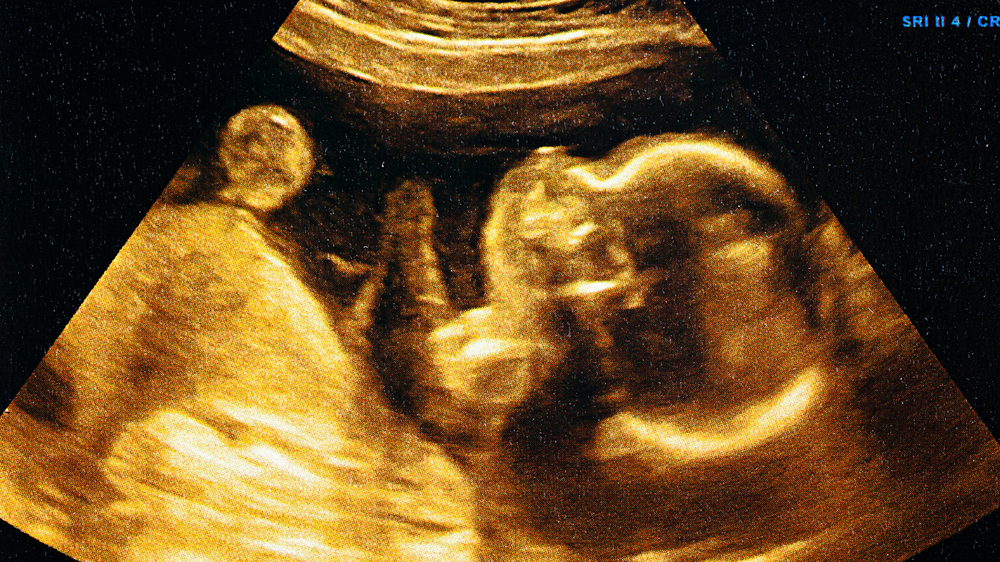

• Ultrasound scans: These measure fetal growth, weight, and amniotic fluid volume.